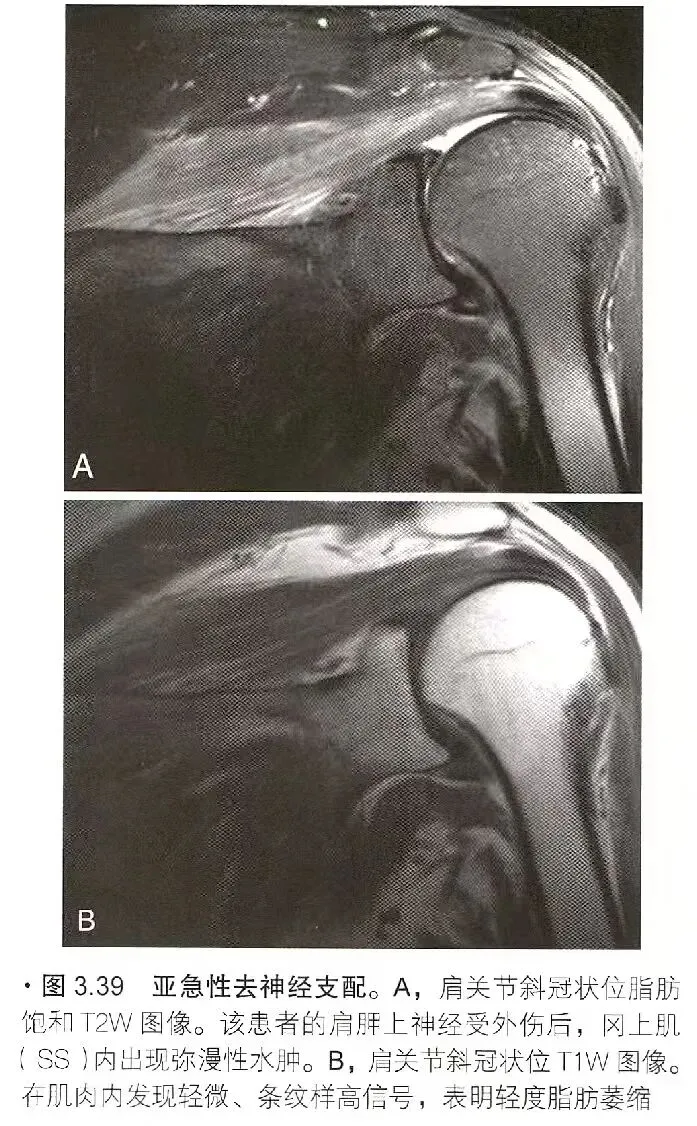

去神经支配